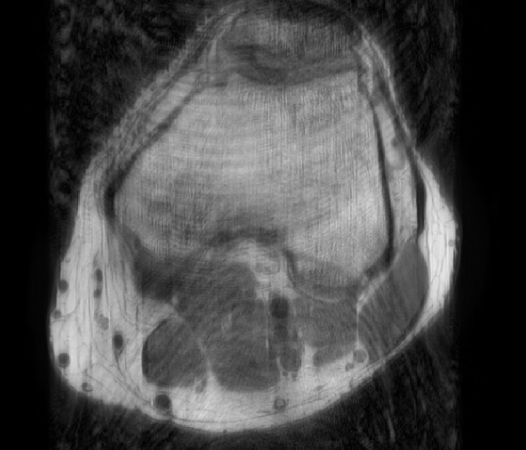

In the example below, only one fifth of the required MR radiofrequency signals is recorded. This results in a five times faster acquisition, with a subsampled k-space (top left) and inherent image artifacts after standard reconstruction (top right).

Basic compressed sensing principle

Philips Compressed SENSE

The Compressed SENSE reconstruction then uses iterative, knowledge-based algorithms to fill in the empty lines in k-space (bottom left). This removes the artifacts while keeping the final image fully consistent with the acquired data (bottom right). *Compared to Philips MR exams without Compressed SENSE